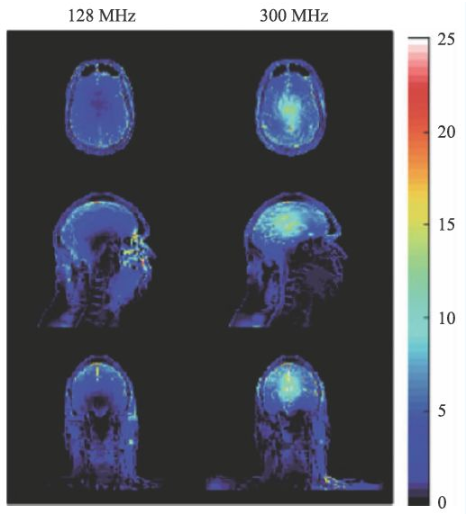

SAR值(zhi)升(sheng)高(gao)是(shi)射頻場另一個問題(ti),隨著(zhu)射頻頻率的(de)提高(gao),組(zu)織對射頻能量(liang)的(de)吸收(shou)急劇上升(sheng),可(ke)導致組(zu)織局(ju)部(bu)的(de)溫度升(sheng)高(gao)。SAR值(zhi)的(de)計(ji)算可(ke)由式9表示。

σ為組織電導率,ρ為組織密度。對于SAR值各國和國際組織均有嚴格的限制,因為過量的射頻能量的吸收可能會對受試者造成危害。

圖14 是一個SAR值對大腦溫度升高的一個仿真結果[14],對于(yu)平均(jun)SAR=3 W/kg的(de)頭部掃(sao)描,7 T(右側(ce))下的(de)溫度升高顯著高于(yu)3 T(左側(ce))。因此在超(chao)高MRI中均(jun)需要配置一個可(ke)靠的(de)SAR值監控裝置。

圖(tu)14 局部SAR值的(de)仿真結果